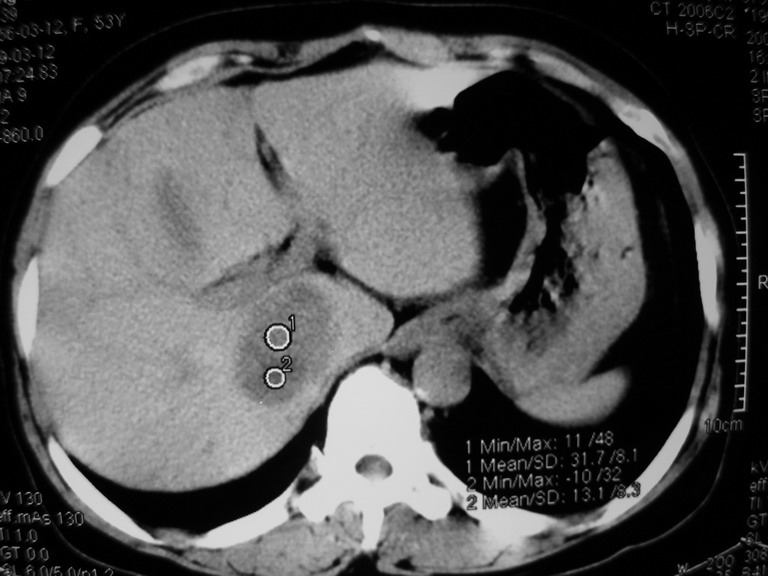

患者,女性50岁,上腹部不适2年余,既往多次腹部彩超未见异常,今日上午在我院查彩超发现肝右叶囊实性病变,外院辅助检查,afp,cea,ca199, 都在正常范围内,无肝炎史否认肿瘤史,生活在牧区

接着往下一贴看,有静脉期和延迟期,在看看和下腔静脉及十二指肠的关系,腔静脉内是不是栓子?

考虑肝右叶与尾叶交界区肝癌(部分外生),侵犯下腔静脉并下腔静脉瘤栓形成。